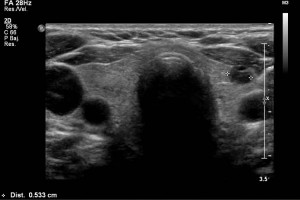

Diplomados en Ultrasonografía